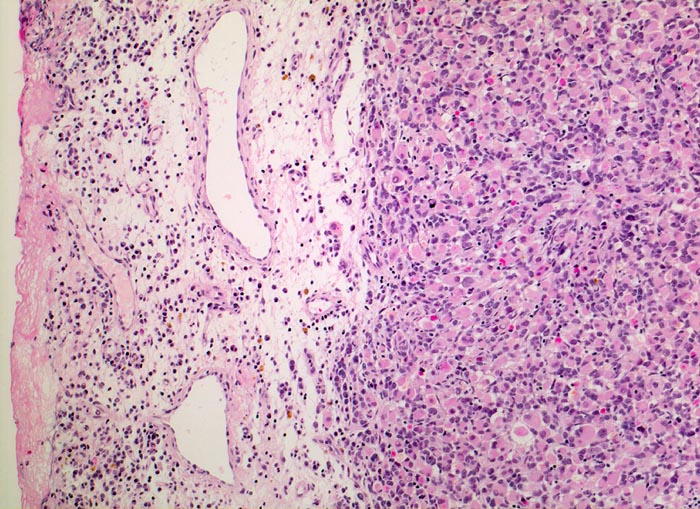

Das makroskopische Bild ist uncharakteristisch und variiert in Abhängigkeit von der Lokalisation. Fokale Nekrosen und zystische Degeneration sind häufig. Es werden verschiedene histologische Subtypen unterschieden, welche charakteristische molekulargenetische Aberrationen aufweisen und mit unterschiedlichen Prognosen assoziiert sind. Die beste Prognose haben botryoide und spindelzellige Rhabdomyosarkome gefolgt von embryonalen Rhabdomyosarkomen (intermediäre Prognose) und alveolären bzw. pleomorphen Rhabdomyosarkomen (schlechteste Prognose). Therapieantwort und Prognose hängen neben der Histologie auch von der Lokalisation ab. Embryonale Rhabdomyosarkome zeigen ein breites morphologisches Spektrum. Dieses reicht von wenig differenzierten Tumoren, die nur mittels Immunhistochemie und Elektronenmikroskopie diagnostizierbar sind zu gut differenzierten Tumoren, die fetaler Muskulatur ähneln. Oft findet sich eine Mischung von wenig differenzierten kleinen, runden und/oder spindeligen Zellen und eine variable Anzahl differenzierter Rhabdomyoblasten mit reichlich eosinophilem Zytoplasma. Die Rhabdomyoblasten können rund, spindelig, kaulquappenförmig oder spinnwebenförmig sein. Besser differenzierte Zellen enthalten reichlich Zytoplasma mit Querstreifung, welche allerdings teilweise nur elektronenmikroskopisch nachweisbar ist.

• Chronisches lymphoplasmazelluläres Entzündungsinfiltrat im subepithelialen Stroma mit unscharfer Begrenzung zu einem zellreichen soliden Tumor.

• Dieser besteht aus mesenchymalen Zellen mit unterschiedlicher Ausdifferenzierung.

• Die am wenigsten ausdifferenzierten Zellen zeigen wenig amphophiles Zytoplasma und ovale Kerne.